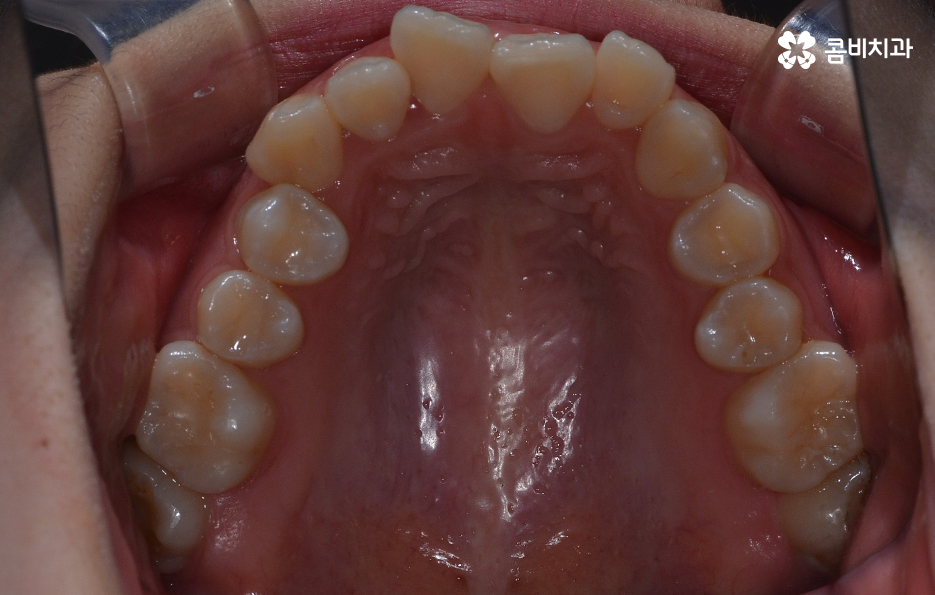

덧니라고 함은 치아의 정상적인 배열에서 많이 벗어난 치아를 의미하고 있는데요. 덧니가 발생하는 원인은 유전적인 원인부터 안좋은 습관 등 다양하겠지만 일반적으로 영구치가 나올 무렵에 치아가 정상적으로 나올 공간이 부족한 상태에서 치아가 맹출되다 보니 덧니가 발생하는 경우가 대표적이라 할 수 있어요

덧니가 심하지 않은 경우에는 비발치로도 충분히 교정을 하는 경우도 있겠지만 덧니가 심한 경우에는 덧니 발치 교정을 통해서 치료가 진행되는 경우가 많이 있는데요. 그 이유는 치아교정의 원리를 생각하더라도 치아를 재배치하기 위해서는 기존의 치아가 움직일 공간이 필요한데 덧니는 치열이 이미 완성되고 있는 상태에서 치아가 나올 공간이 부족하여 덧니가 되는 경우가 많다는 점에서도 치아의 이동 공간을 확보하기 위한 발치가 필요할 수 있는 거예요

물론 치아의 이동 공간을 조금만 확보하면 되는 경우에는 악궁 확장이나 치간 삭제와 같은 방법으로도 치아의 이동 공간을 확보하여 비발치로 치아교정이 가능한 사례도 있지만 덧니 교정을 통해서 부정교합과 함께 얼굴형의 변화까지 치료 목적으로 하는 경우에는 발치가 필요한 경우가 많다고 볼 수 있어요